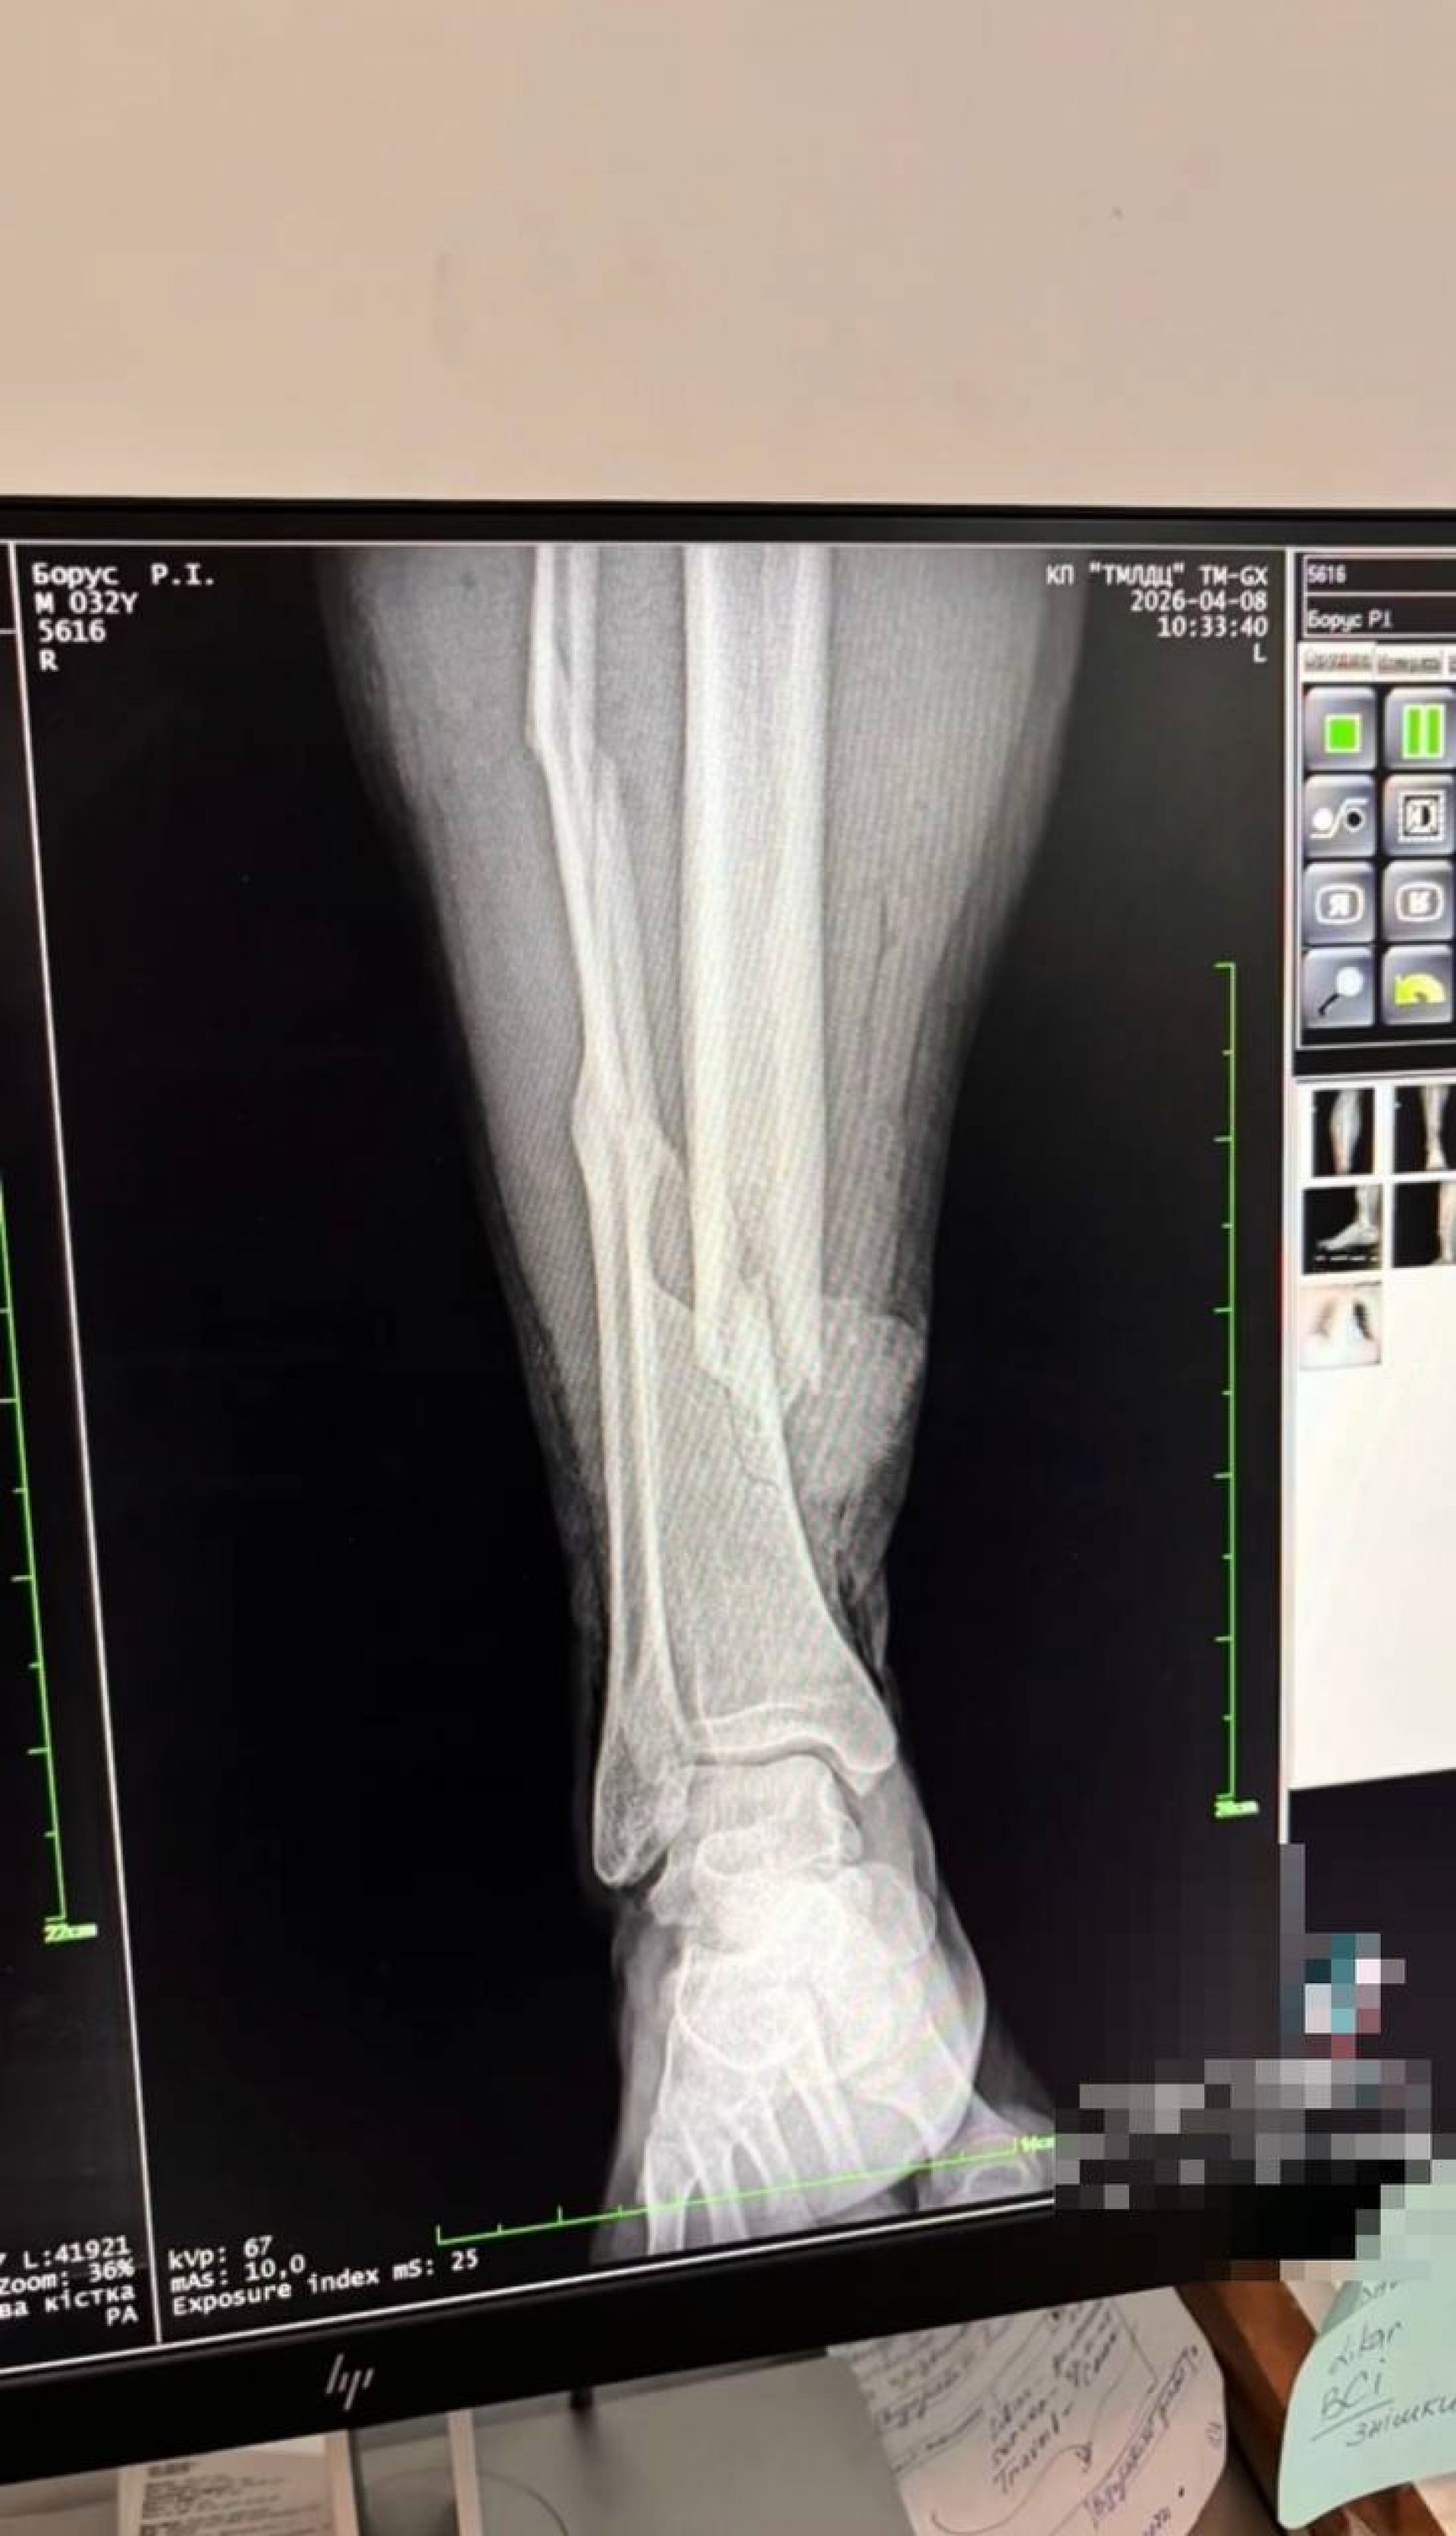

За словами двоюрідного брата, постраждалому вже провели операцію на ногу. Також у соціальних мережах дружина опублікувала рентгенографічні знімки ноги чоловіка після побиття.

За зверненням редакції «20 хвилин» у Спеціалізованій прокуратурі у сфері оборони Західного регіону прокоментували, що інформація про інцидент на вулиці Сахарова, де троє працівників ТЦК та СП завдали тілесних ушкоджень 32-річному місцевому жителю, надійшла 8 квітня орієнтовно о 10:20. У потерпілого діагностували відкритий перелом лівої великогомілкової кістки.